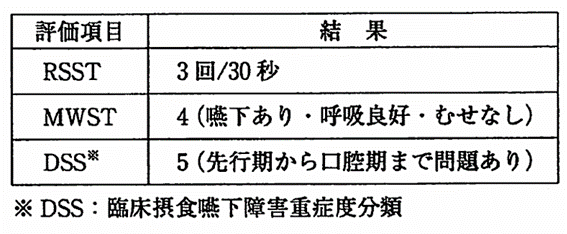

午前-88

80歳の女性。舌癌に対する舌部分切除術後2週が経過した。現在在宅療養中である。体重に変化はないという。経口摂取を進めるために評価を行った結果を表に示す。患者に対する適切な指導はどれか。2つ選べ。

a.ゆっくり食べましょう。

b.一口の量を少なめにしましょう。

c.栄養補助食品を中心に食べましょう。

d.口を大きく開かないようにしましょう。

解答を見る

a.b